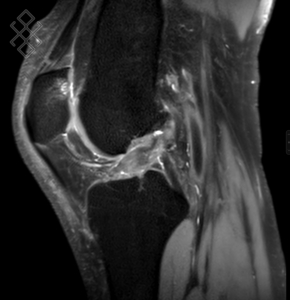

IRM du Genou